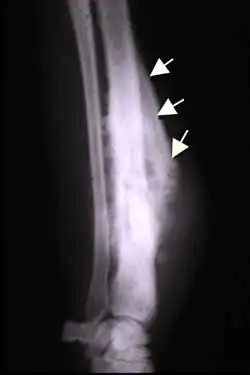

The Codman triangle (previously referred to as Codman's triangle) is the triangular area of new subperiosteal bone that is created when a lesion, often a tumor, raises the periosteum away from the bone.[1] A Codman triangle is not actually a full triangle. Instead, it is often a pseudotriangle on radiographic findings, with ossification on the original bone and one additional side of the triangle, which forms a two sided triangle with one open side. This two sided appearance is generated due to a tumor (or growth) that is growing at a rate which is faster than the periosteum can grow or expand, so instead of dimpling, the periosteum tears away and provides ossification on the second edge of the triangle.[2] The advancing tumour displaces the periosteum away from the bone medulla. The displaced and now lateral periosteum attempts to regenerate underlying bone. This describes a periosteal reaction.

The main causes for this sign are osteosarcoma, Ewing's sarcoma, eumycetoma, and a subperiosteal abscess.[3][4]